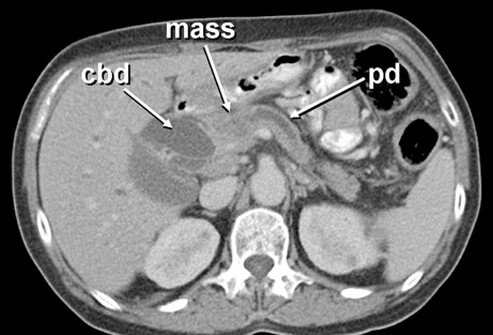

- CT scans: these are types of X-rays that show cross sections of the body and can also help determine if the cancer has spread to other organs.

- Image reprinted courtesy of eMedicine, 2009